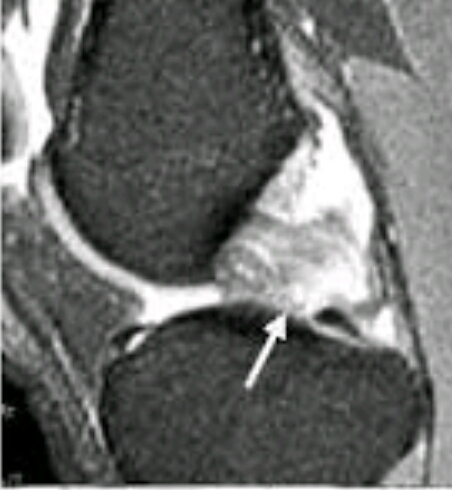

Name the problem.

medial meniscus tear